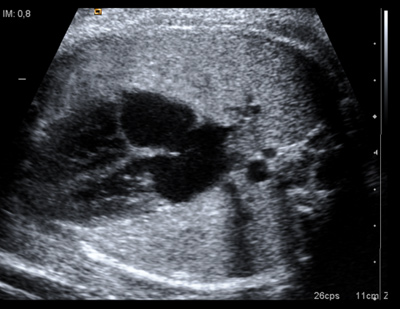

AS SE VE UN EMBARAZO DE 4 SEMANAS DE GESTACI N YouTube

El ultrasonido temprano en el embarazo

Product Name: Test de embarazo positivo y no se ve nada en la ecografia dealsTest positivo y en ecograf a no se vio nada BabyCenter deals, Test positivos pero no se ve nada en la eco BabyCenter deals, Prueba de sangre positiva y en el eco no se ve nada BabyCenter deals, Prueba de sangre positiva y no se ve nada en la eco BabyCenter deals, prueba de sangre positiva no se ve nada en el ultrasonido deals, No se vio ni saco gestacional en la eco pero test positivo deals, Prueba de sangre positivo Nada en ecograf a BabyCenter deals, EMBARAZO DE 4 SEMANAS PRUEBA DE EMBARAZO POSITIVA Y NO SE VE SACO deals, En las pruebas de sangre sale que si estoy embarazada pero en el deals, prueba de embarazo positiva y no se ve nada en el deals, Prueba positiva en ultrasonido no se ve embarazo BabyCenter deals, Ecograf a de las 5 semanas No he visto al beb y ahora qu deals, Embarazo Anembrionario deals, prueba negativa pero eco positivo BabyCenter deals, La primera ecograf a qu pasa cuando no se ve el embri n deals, AS SE VE UN EMBARAZO DE 4 SEMANAS DE GESTACI N YouTube deals, EMBARAZO DE 4 SEMANAS PRUEBA DE EMBARAZO POSITIVA Y NO SE VE SACO deals, prueba de embarazo de eco B squeda de TikTok deals, C mo funciona un test de embarazo farmacias ecoceutics deals, EMBARAZO DE 4 SEMANAS PRUEBA DE EMBARAZO POSITIVA Y NO SE VE SACO deals, TEST DE EMBARAZO PUEDE HABER FALSO POSITIVO Y NEGATIVO Blog deals, Semana 6 de embarazo evoluci n del embri n y s ntomas deals, Semana 5 de embarazo desarrollo del beb y s ntomas en la madre deals, Todo lo que necesitas saber sobre el test de embarazo Matronastur deals, Respuesta a miguelinaperez431 gestaciondelocalizacionincierta es cuando tenemos un testdeembarazopositivo pero no vemos nada en la ecografia Para ello habra que determinar los niveles de bhcg en deals, Puede fallar el test de embarazo Natalben deals, Prueba de embarazo con linea tenue qu significa deals, Cuando hacer un test de embarazo tras una FIV Barcelona IVF deals, EDSONGCANO PRUEBA DE EMBARAZO POSITIVA Y ULTRASONIDO NORMAL deals, Test de embarazo positivo todo lo que debes saber deals, QU ES UN EMBARAZO QU MICO TEST EMBARAZO POSITIVO deals, S ntomas de embarazo pero test negativo posible falso negativo deals, L nea de Evaporaci n en el Test de Embarazo Gu a deals, Beta baja y embarazo evolutivo preguntas y respuestas deals, Carlos Zavala MD OBGYN zavalamdobgyn s videos with original sound Carlos Zavala MD OBGYN TikTok deals, Emocionante primera ecograf a del embarazo Cu ndo se hace y qu deals, Son fiables los tests de embarazo deals, Todo lo que necesitas saber sobre el test de embarazo Matronastur deals, Mi duelo MAMIfit ES deals, Ecograf a transvaginal Salud Femenina deals, Cu ndo podr a dar positivo un test de embarazo de alta sensibilidad deals, Errores al hacer un test de embarazo Puede dar un falso negativo deals, AS SE VE UN EMBARAZO DE 4 SEMANAS DE GESTACI N YouTube deals, C mo funciona el test que averigua la madurez pulmonar fetal deals, Respuesta a albitamansanita2 Tienes un examen de embarazo deals, Beta negativa y embarazo es posible deals, El ultrasonido temprano en el embarazo deals, INCERTIDUMBRE AGRIDULCE EN NAVIDAD Laia Rovira deals, Cuando hacer un test de embarazo tras una FIV Barcelona IVF deals, Todo lo que necesitas saber sobre el test de embarazo Matronastur deals.